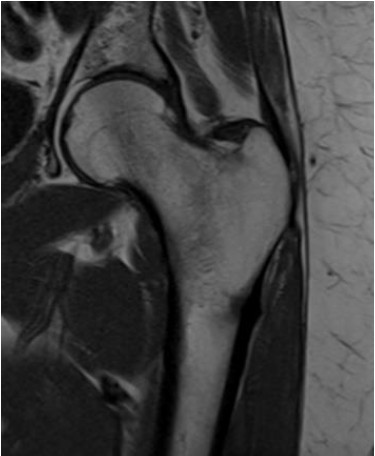

Observe o caso clínico a seguir.

Paciente de 56 anos com dor no quadril após queda realizou exame para elucidação diagnóstica demonstrado na imagem abaixo.

De acordo com a imagem, o exame realizado e o plano de aquisição são, respectivamente: